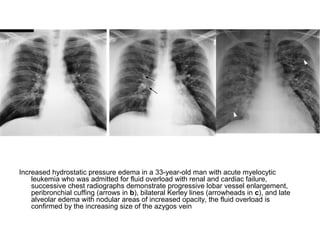

Increased hydrostatic pressure edema in a 33-year-old man with acute myelocytic

leukemia who was admitted for fluid overload with renal and cardiac failure,

successive chest radiographs demonstrate progressive lobar vessel enlargement,

peribronchial cuffing (arrows in b), bilateral Kerley lines (arrowheads in c), and late

alveolar edema with nodular areas of increased opacity, the fluid overload is

confirmed by the increasing size of the azygos vein